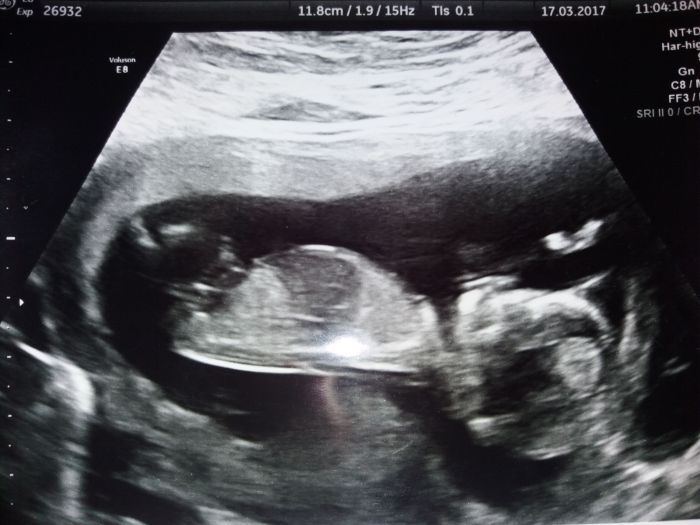

cekam na utz srdicka ve 20tt kde budu vedet s jistotou,co to je

termim mi zas posunuli,takze 19.9.me mico.spinkalo,takze jsem musela chodit po schodek,aby se probralo a otocilo se na zada